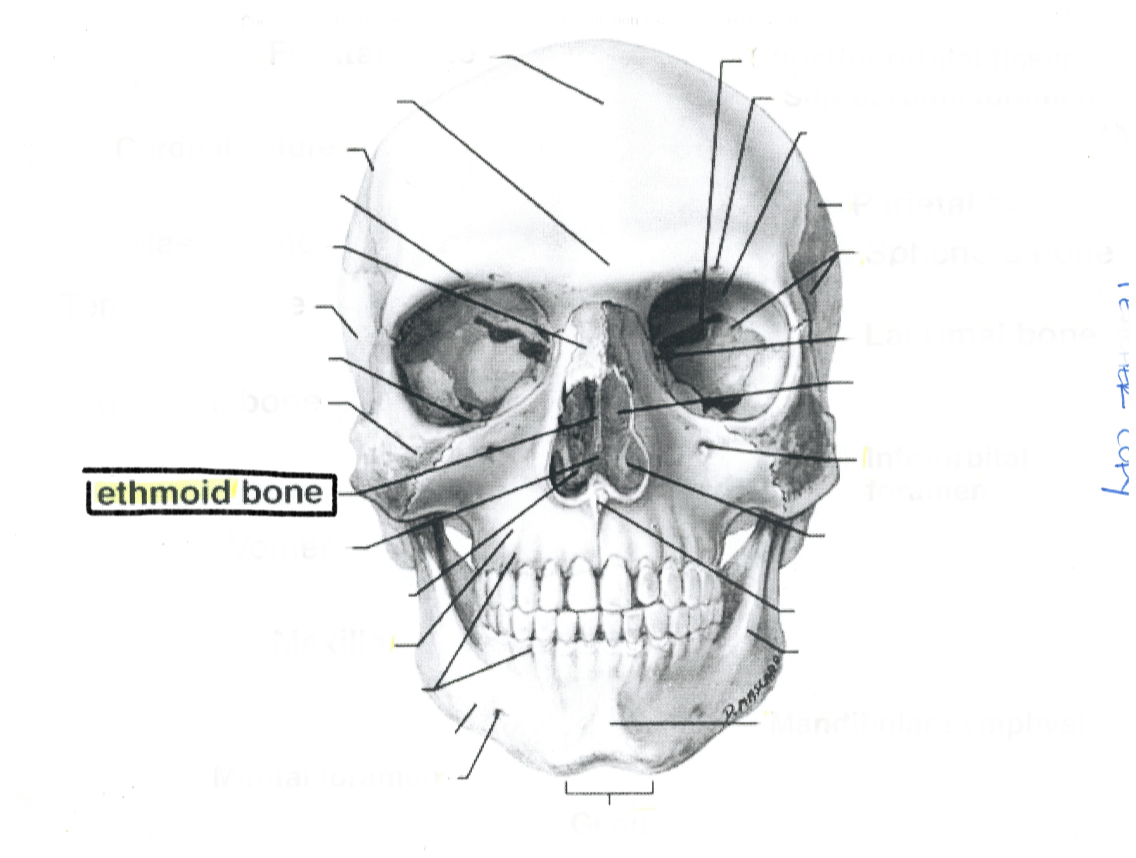

Ethmoid bone

Ethmoid